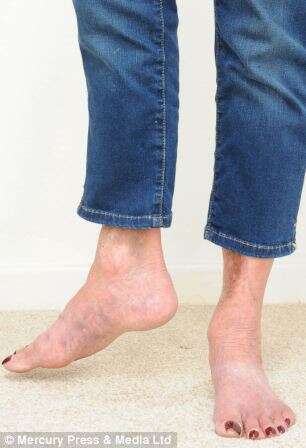

Uma idosa que ficou com o pé virado 90 graus na direção errada após um cirurgião realizar uma operação errada, ganhou cerca de 950 mil reais em danos.

A dor e o inchaço na perna não diminuíram, e uma operação de revisão foi proposta. Ela disse: “Depois da segunda operação, tornou-se óbvio que o meu pé direito começou a apontar para o Leste. Eles tentaram colocar meu pé em linha reta usando sacos de areia.”

Gorst disse: “Eu estava com dor aguda, hematomas e inchaços eram terríveis, e minha perna estava torcida inteiramente na direção errada. Minha perna é praticamente inútil. Eu saí de alguém que estava ativa para alguém que não é capaz de fazer muitas das coisas que costumava fazer.”

A substituição da anca já foi removida, mas seu osso da perna é agora fundido à pelve, encurtando a perna da mulher em 10 centímetros.